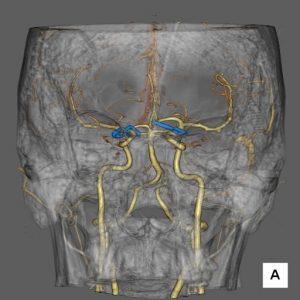

血管撮影検査

腕や足の比較的太い血管からカテーテルと呼ばれる細い管を入れ、心臓や脳、腹部の血管など選択的に挿入し、その先から造影剤を注入し、造影された血管の走行状態、病変まで撮影、治療を行います。

心臓用、頭部用、腹部用(+IVRCT)、ハイブリッド血管撮影装置の4台の装置が稼働しており、緊急検査・治療にも対応しています。